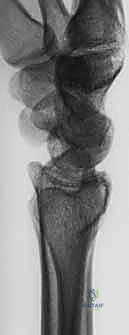

عند حدوث التئام معوج (Malunion)، تتغير هذه الزوايا. على سبيل المثال، إذا فقدت الكعبرة طولها (أصبحت أقصر من الزند)، فإن عظم الزند سيصطدم بعظام الرسغ الصغيرة (Ulnar Impaction Syndrome)، مما يسبب تمزقاً في الغضروف الثلاثي (TFCC) وألماً مبرحاً عند دوران اليد.

- تشوه شكلي واضح: ظهور اليد بشكل "ظهر الشوكة" (Dinner Fork Deformity) حيث يبدو الرسغ متعرجاً بشكل غير طبيعي.